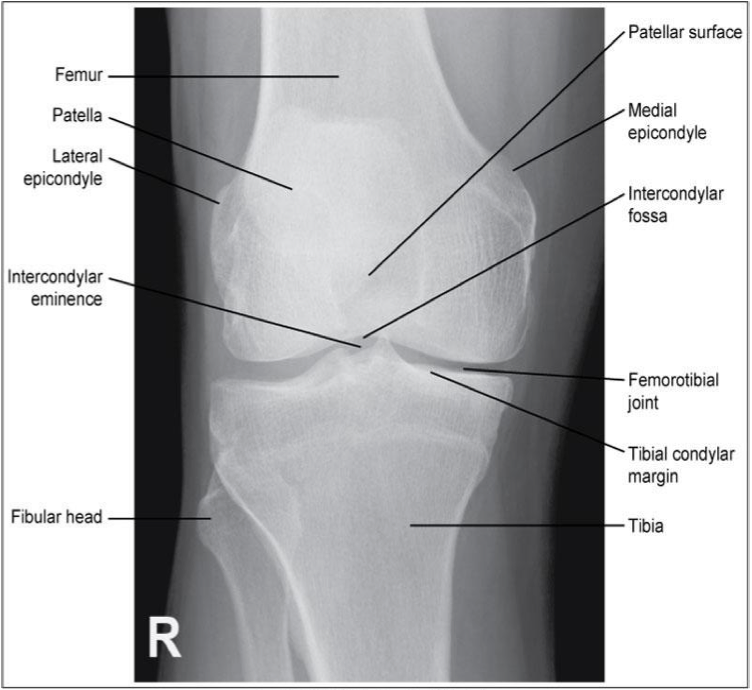

Evaluation Criteria for AP knee

• Femorotibial joint space open

• Femoral condyles are symmetrical

• Femoral epicondyles in profile

• Knee joint centered to collimation field

• Articular facets of tibia on end

• Intercondylar eminence centered within the fossa

• Intercondylar fossa is barely seen

• Approx ½ of fibular head superimposed by tibia

• Head of fibula approx 1.25 cm from tibial plateau

• Patella sits slightly lateral to midline